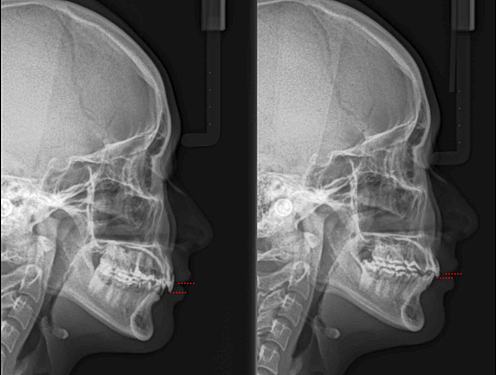

骨暴、笑時露很多牙齦等矯正醫師心目中的難症,

以前只能倚靠正顎手術在有了迷你骨釘的出現,便可以藉由骨釘協助牙齒做大量移動而改善。

林醫師在演講中也分享了改良式的前牙上壓方式,可以降低患者對於傳說中人中骨釘不適的害怕。